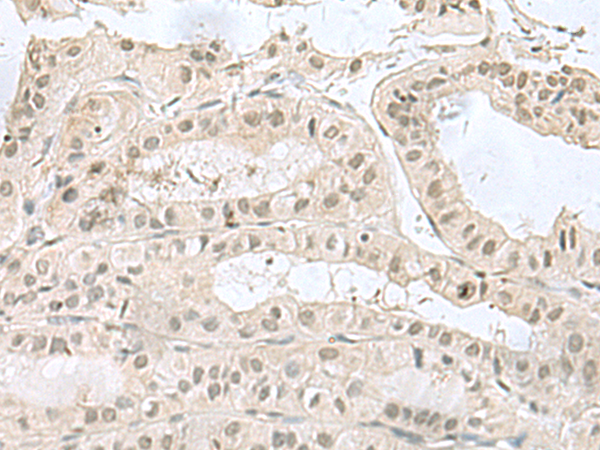

分类: 科研抗体货号: P10225别名: ISK; JLNS; LQT5; MinK; JLNS2; LQT2/5应用: IHC反应种属: Human